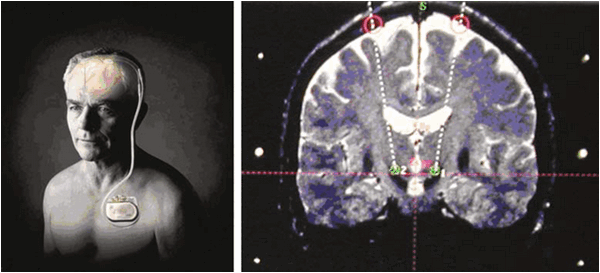

Также он является пионером использования ГСМ в лечении психических заболеваний - в 1948 году он установил электрод для стимуляции в правое хвостатое ядро женщины, страдающей депрессией. Симптоматика редуцировалась в течение 8 недель [3].

Десмонд Келли и Алан Ричардсон разрабатывают лимбическую лейкотомию в 1973 г.: лимбическая лейкотомия по сути является сочетанием передней цингулотомии и субкаудатной трактотомии и предназначалась в первую очередь для избегания повторных операций по поводу рецедивов депрессии и ОКР. Наиболее перспективным методом лечения на сегодня является не деструкция, а стимуляция различных анатомических структур, часть из которых является целью и для деструкции.

Пример ГСМ с мишенью в Льюисовом теле для лечения болезни Паркинсона, ОКР и депрессии [1,2].